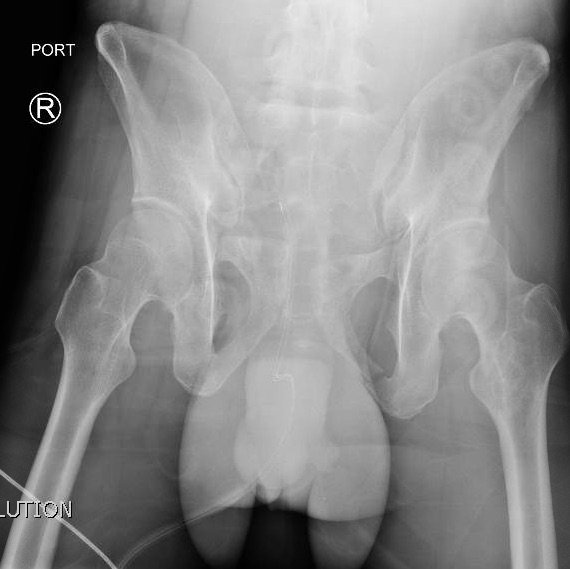

The initial radiograph of the pelvis shows an open-book pelvic fracture deformity with pubic symphyseal dislocation, left greater than right sacroiliac diastases, and fractures of the left superior and inferior pubic rami, right inferior pubic ramus, and left acetabular anterior column. The additional inlet and outlet radiographs of the pelvis after application of a pelvic binder also show an open book fracture with significant improvement of the widened pubic symphysis.

Severe pelvic injuries, including open book dislocations, have a high mortality rate of 10.4%.1,2 The mechanism is commonly a motor vehicle collision or fall from a significant height.3 Open book dislocations of the pubic symphysis are rare, representing 0.3–8.2% of all fractures,4,5 and can lead to fatal complications through vascular, abdominal, and nervous injuries.6 In severe pelvic traumas, pelvic binders must be applied as soon as possible to reduce bleeding by realigning fracture surfaces and provide stabilization of unstable fractures.7,8 Open book dislocation can be identified via plain anteroposterior pelvis radiographs.9 Definitive treatment of open book dislocations are highly individualized and come secondary to controlling hemorrhagic bleeding. The most common method is open reduction and internal fixation (ORIF) although in some cases, external fixation can be sufficient to stabilize the pelvis.10 Our patient was admitted for multiple traumatic injuries and underwent closed reduction and percutaneous fixation of posterior pelvic ring, including bilateral sacroiliac joints, and ORIF of the pubic symphysis.